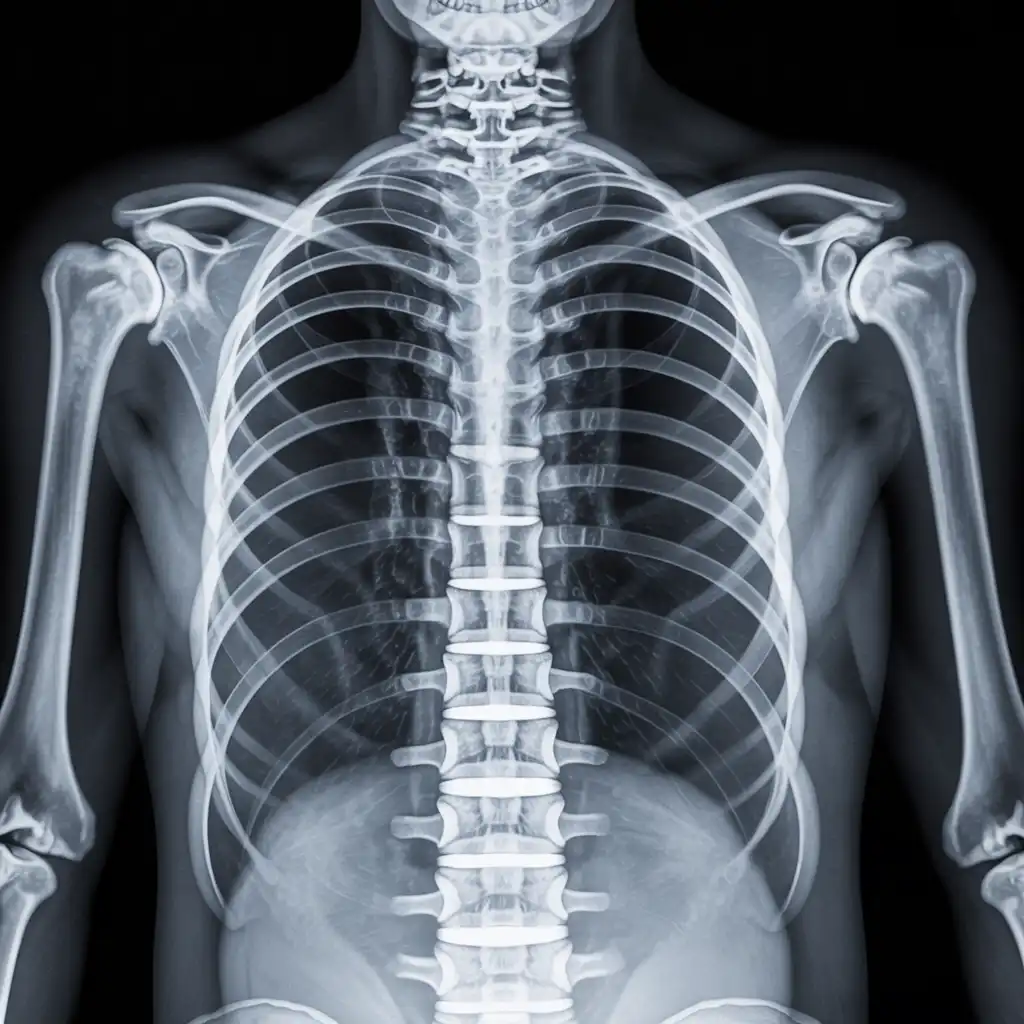

Una radiografia a domicilio è un esame radiologico eseguito da un tecnico specializzato che viene a casa tua con apparecchiature digitali portatili. L’esame si svolge sul posto, senza spostare il paziente e con la stessa qualità di una struttura ospedaliera.

Siamo un team di tecnici radiologi qualificati con anni di esperienza maturata in strutture sanitarie di Pescara e provincia. Abbiamo scelto di portare la diagnostica direttamente nelle case dei pazienti, offrendo radiografie a domicilio con la stessa precisione degli esami eseguiti in ambulatorio, ma con tutta la comodità del proprio ambiente. Nel tempo abbiamo eseguito migliaia di esami a domicilio in abitazioni private, residenze per anziani e centri assistenziali, utilizzando apparecchiature digitali portatili certificate e procedure rapide, sicure e adatte anche ai pazienti con difficoltà di movimento. Con Radidom Pescara mettiamo al centro la persona: competenza, cura e tecnologia al servizio della tua salute, ovunque tu sia.